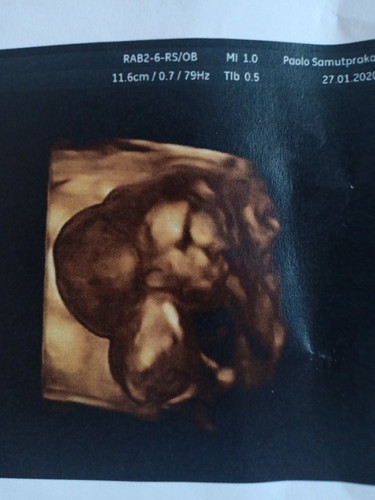

ซาวด์มาแล้วเจอถุงแบบนี้

ไม่รู้จะทำยังไง หมอบอกจะซาวด์ละเอียดให้อีกทีแต่อ่านในเนตคือไม่โอเคทั้งนั้น